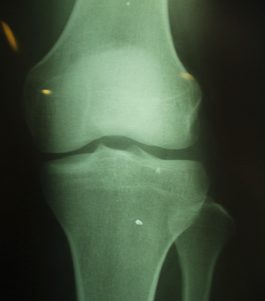

X-ray로 성장판을 검사하면 손이나 골반, 무릎관절, 팔꿈치관절, 발목관절을 사용해서 골연령을 평가하는데요.

성장판 검사는 나이에 따라 검사 부위가 다른데 청소년의 경우 어깨를 같이 찍기도 하고, 1세 미만의 경우 무릎 사진을 같이 찍기도 합니다.